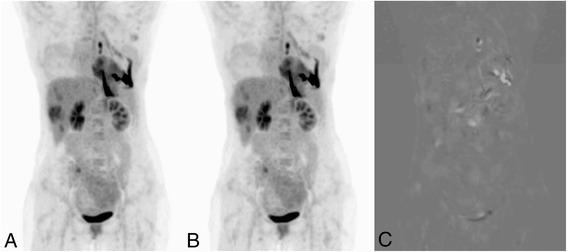

Evaluation of the elastix toolbox was performed using (18)F-FDG PET/CT at baseline and after 2 cycles of therapy (follow-up) data in advanced NSCLC patients. The elastix toolbox, an integrated part of the IMALYTICS workstation, was used to apply a CT-based non-linear image registration of follow-up PET/CT data using the baseline PET/CT data as reference. Lesion statistics were compared to assess the impact on therapy response assessment. Next, CT-based deformable image registration was performed anew on the deformed follow-up PET/CT data using the original follow-up PET/CT data as reference, yielding a realigned follow-up PET dataset. Performance was evaluated by determining the correlation coefficient between original and realigned follow-up PET datasets. The intra- and extra-thoracic tumors were automatically delineated on the original PET using a 41% of maximum standardized uptake value (SUVmax) adaptive threshold. Equivalence between reference and realigned images was tested (determining 95% range of the difference) and estimating the percentage of voxel values that fell within that range.

Thirty-nine patients with 191 tumor lesions were included. In 37/39 and 12/39 patients, respectively, thoracic and non-thoracic lesions were evaluable for response assessment. Using the EORTC/SUVmax-based criteria, 5/37 patients had a discordant response of thoracic, and 2/12 a discordant response of non-thoracic lesions between the reference and the realigned image. FDG uptake values of corresponding tumor voxels in the original and realigned reference PET correlated well (R (2)=0.98). Using equivalence testing, 94% of all the voxel values fell within the 95% range of the difference between original and realigned reference PET.